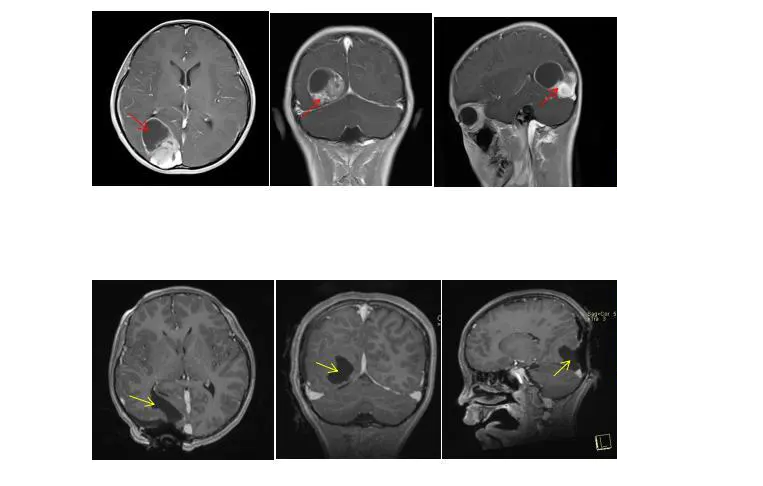

病史:患者近半月来频繁头痛,MRI检查:右侧枕叶、颞叶4.0*3.9*4.0cm囊实性占位,多考虑胚胎来源肿瘤。患者无发热,呕吐等情况,神经系统查体无明显阳性体征。

术前影像:右侧枕颞叶囊实性占位,边界清晰,囊壁及实性部分强化明显。

术前术后影像对比: